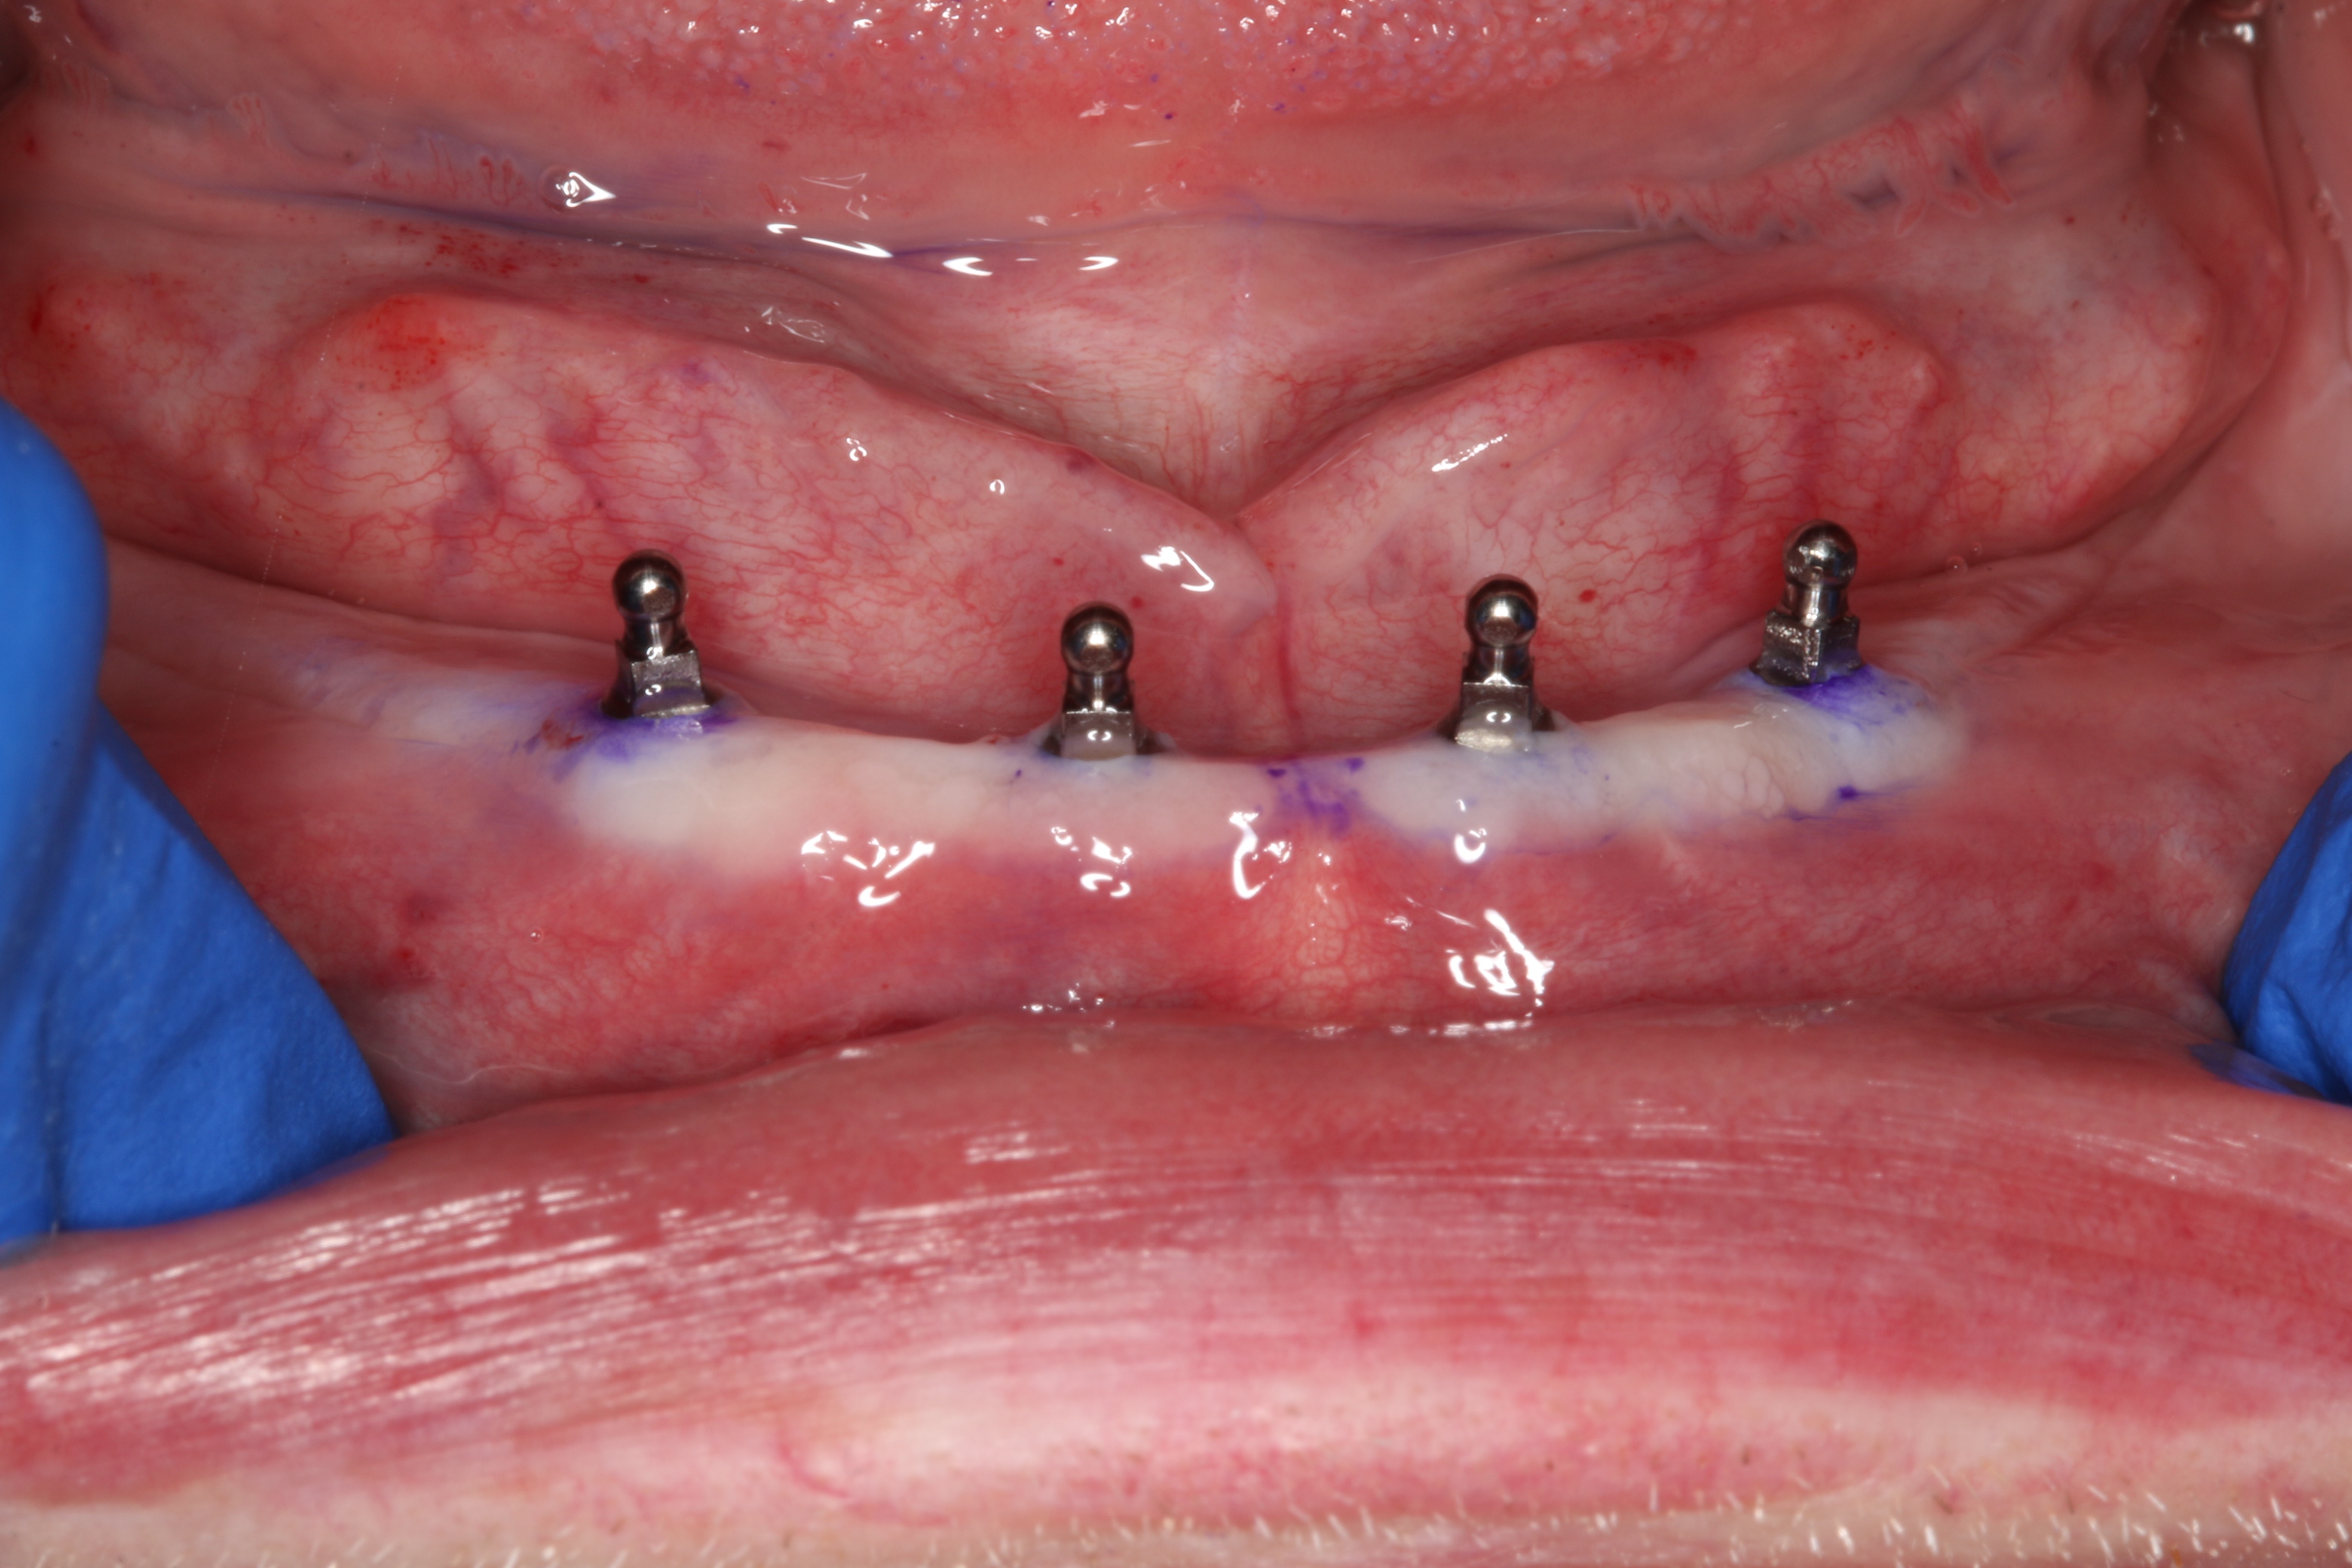

At 6 weeks post-surgery the implants showed proper healing (Figure 14) and the denture was delivered (Figure 15). Overpressurized areas that create sore spots were identified and adjusted as needed.

Fig 14. At 6 weeks postoperative, healing of implants with healthy surrounding tissue can be seen.

Figure 14